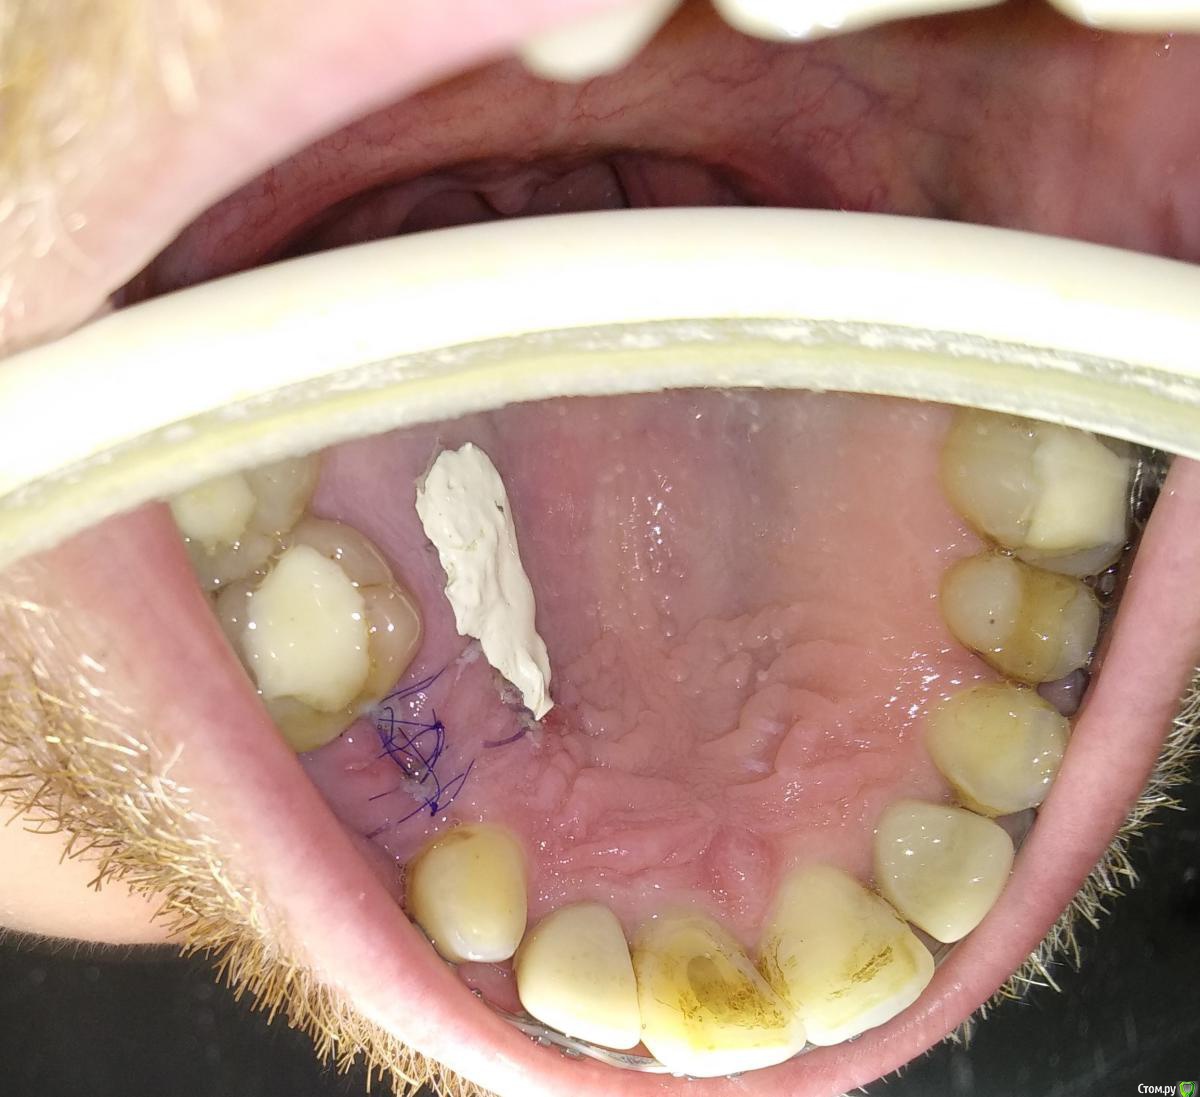

Al..ks Опубликовано 2 июня, 2019 Поделиться Опубликовано 2 июня, 2019 Прошла 30 мая имплантация 14 (3,5*9 Astra + заглушка - торк слабый. Изначально планировался сразу формирователь, но этот вариант мне больше по душе) + подсаживали десну к 16 (снимки КТ чуть позже добавлю). Пил сумамед, немисил (гадость походу - кишки крутило с него), лоратадин - три дня. Сейчас только ванночки хлоргексидина (хотя хирургическая щетка лежит с 12тыс щетинками, но забыл когда ей пользоваться начинать) Была слегка припухлость - на сегодня начала спадать остался только желтый синяк (как его побыстрее свести?)Вопрос по десне я правильно понимаю, что в районе швов это фибриновый налет? А вокруг 16-17 это тоже самое или пора панику наводить? Спасибо за ответы Ссылка на комментарий